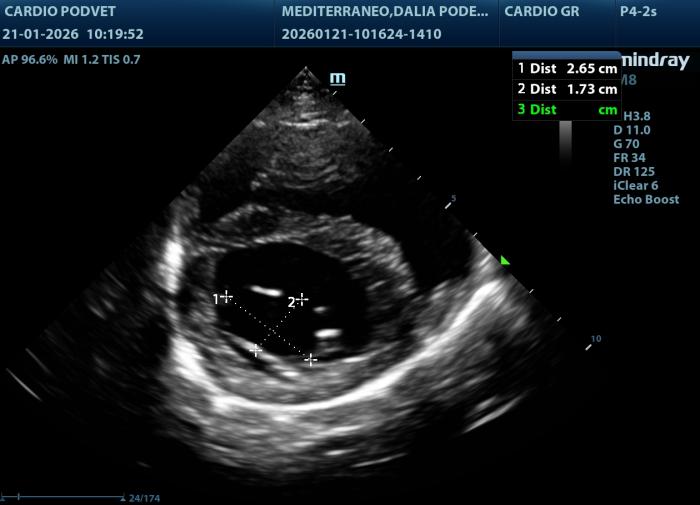

Posteriormente se obtiene este índice mediante la siguiente fórmula: LAI= AML (mm) + PML (mm)]/APL(mm). El área mitral se calcula obteniendo los diámetros de la válvula mitral (AM) en la vista paraesternal derecha transversal a la altura de la válvula mitral, con los diámetros anteroposterior (dAP) y diámetro transcversal (dT) (Figura2) y la fórmula: AM = (π x (dAP/2) x (dT/2))/100. Y por último los diámetros y áreas de las valvas mitrales medidas en la vista paraesternal derecha 4 cámaras durante la diástole (Figura3A-B).